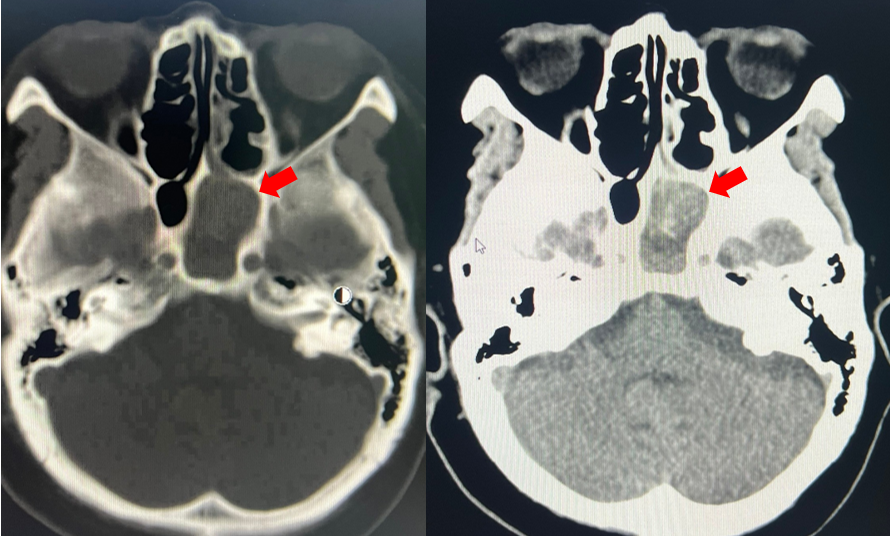

Hình ảnh khối nấm xoang bướm bên trái (mũi tên đỏ) - Ảnh: Bệnh viện Nhân dân 115

Qua thăm khám, chụp CT scan mũi xoang và cận lâm sàng, các bác sĩ xác định bệnh nhân mắc viêm xoang bướm trái do nấm kèm nhiễm trùng xoang bướm.